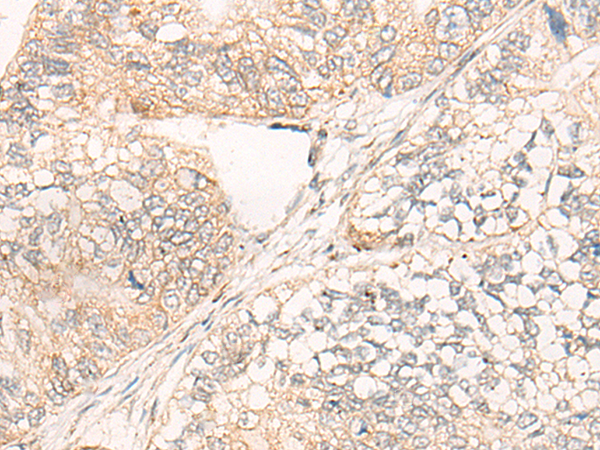

IHC positive control: |

Human gastric cancer |

IHC Recommend dilution: |

20-100 |